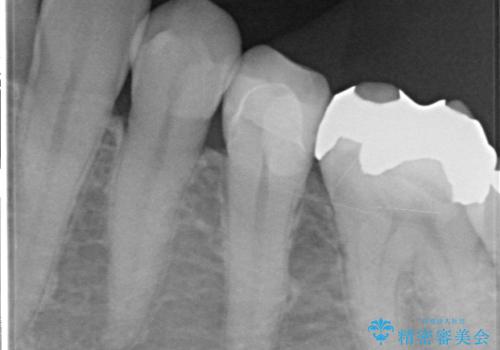

銀歯が外れ、内部に大きな虫歯の再発

- 20年ほど前に治療した虫歯が脱離し、内部には大きな虫歯が認められました。

神経を保存できるよう丁寧に虫歯を除去し、セラミックによる機能回復を計画します。

老朽化した銀歯の下には虫歯の再発リスクが潜んでいます。定期的なX線写真検査が早期発見に有効です。